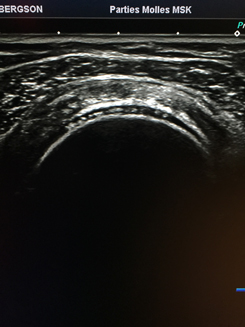

L'exploration se fait à l'aide d'une sonde qui émet et reçoit les ultrasons, et permet, via un gel permettant l'interface avec la peau, d'explorer des organes profonds (foie, reins, rate, pancréas, vésicule, aorte , utérus , ovaires, vessie etc...) comme des organes superficiels (tendons, muscles , nerfs, thyroïde, seins, ganglions, articulations, etc... ).